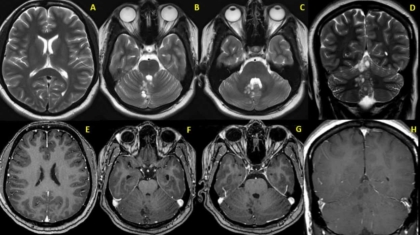

A 30 year old female with headache. What is the diagnosis?